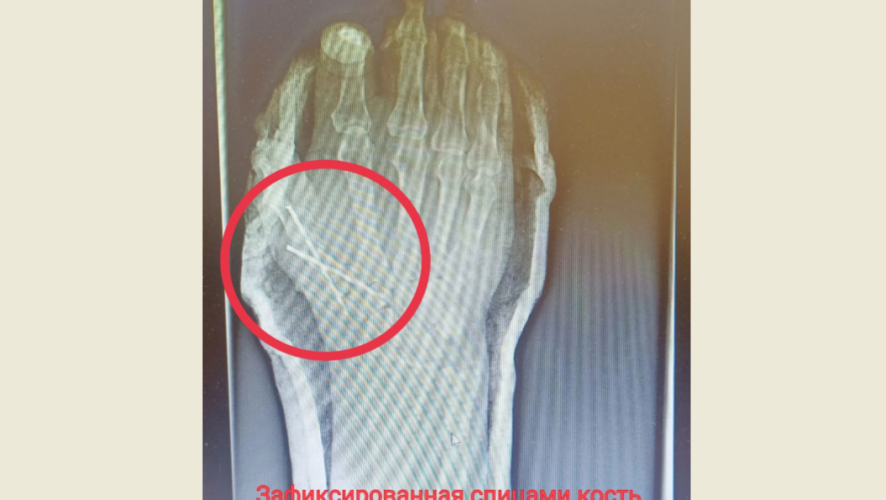

В экстренном порядке мужчину прооперировал врач травматолог-ортопед Марат Шахбанов, ему помогала операционная медицинская сестра Энже Газизова. Травма оказалась сложной, пациент мог лишиться большого пальца, который почти полностью был отрезан от руки. Врач восстановил сначала пястную кость, зафиксировав ее спицами, после восстановил сухожилия. Операция продлилась два с половиной часа.